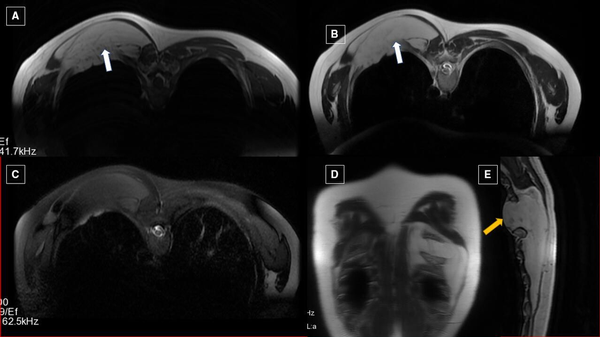

Plain radiograph of the right chest revealed normal study. MRI of the left scapula revealed a hyperintense lesion (12×1.7×12 cm) on the left paravertebral region extending from D5 to D12, which is suppressed on STIR sequence (figure 1). The lesion was also extending into the fifth intervening intercostal space, causing its widening due to mass effect. Visualised vertebral bodies showed normal signal intensity and morphology. The final impression of MRI was lipoma. Tru-cut biopsy was performed which was suggestive of lipoma.

Figure 1

Axial T1WI (A) and T2WI (B) showing hyperintense lesion (marked by white arrow) in the left paravertebral region extending from D5 to D12 levels, which is suppressed on fat suppressed sequence, that is, stir (C). Corresponding coronal (D) and sagittal (E) T2WI showing the extent of the lesion. Protrusion of lipoma causing intercostal widening is marked by yellow arrow (WI—weighted image, STIR—short τ inversion recovery sequence).